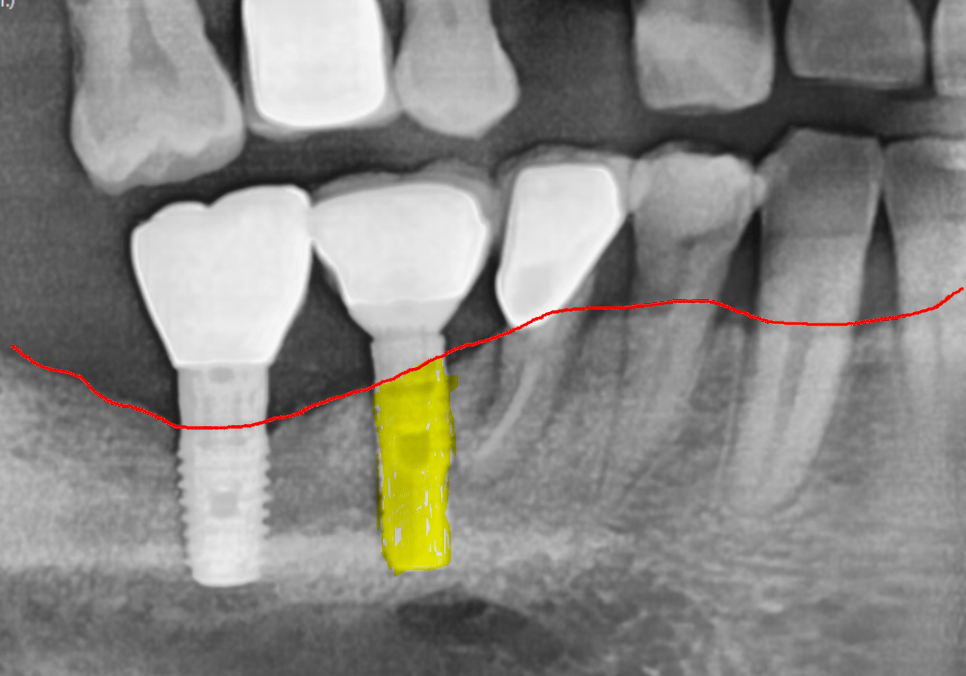

천만다행으로 임플란트의 뿌리 역할을 하는

'픽스처'와 잇몸뼈는

아주 튼튼하게 잘 붙어있었어요.

보통 임플란트가 흔들리는 이유는

크게 두 가지입니다.

염증이 생겨서 임플란트를 지탱하던

뼈가 스르르 녹아버린 경우입니다.

사실 이게 제일 골치 아픈 문제입니다.

뼈는 멀쩡한데,

머리 부분을 연결하는

나사가 풀린 경우에도

임플란트가 흔들릴 수 있습니다.

이 경우는 나사만 조이면 해결됩니다.

다행히 이 환자분은 뼈에는 문제가 없는

단순 '나사 풀림' 케이스였습니다.